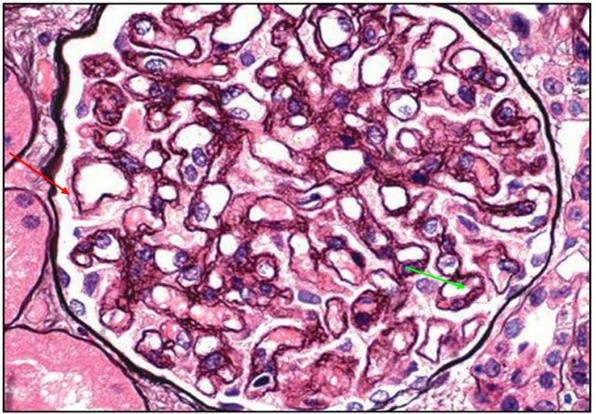

#肾脏病##膜性肾病#

虽然PLA2R抗体在膜性肾病的诊断中有重要意义,但是PLA2R抗体阴性并不能排除膜性肾病可能,也不能区分患者目前处于膜性肾病的几期(膜性肾病在病理下可分为四期),所以PLA2R抗体存在着一些限制,如果患者无明显肾穿刺禁忌,还是建议能进行肾穿刺最好,因为肾穿刺是肾炎患者的诊断金标准,不仅可以明确病理类型及分期,还能判断出患者的预后情况。